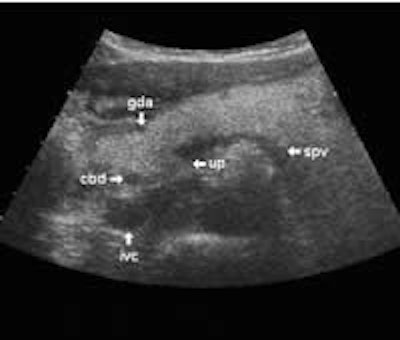

The following study describes anatomical landmarks in the ordinary pancreas of a thin patient:

Transverse planes in caudal direction:

The dorsal aspect of the head takes the shape of a hook surrounding the right side of the superior mesenteric vein; the sharp left-pointing tip of the hook behind the vein constitutes the uncinate process. The splenic vein runs from the left along the dorsal border of the tail and body to the superior mesenteric vein, where these veins join to form the portal vein behind the "neck" of the pancreas. The portal vein then leaves the pancreas to the right and slightly upwards and runs into the liver hilum.

The main bile duct runs from the liver hilum to the right of and above the portal vein into the right dorsal part of the pancreatic head, where it runs vertically into the duodenum. The pancreatic duct typically runs along the body and tail to join the common bile duct near the duodenum. The gastroduodenal artery is sometimes seen in its position along the front margin of the pancreatic head, where it runs in a nearly parallel direction to the common bile duct. Like the common bile duct and pancreatic duct, however, the gastroduodenal artery is not always clearly seen due to its small diameter. The duodenum covers the right and bottom margins of the pancreatic head.